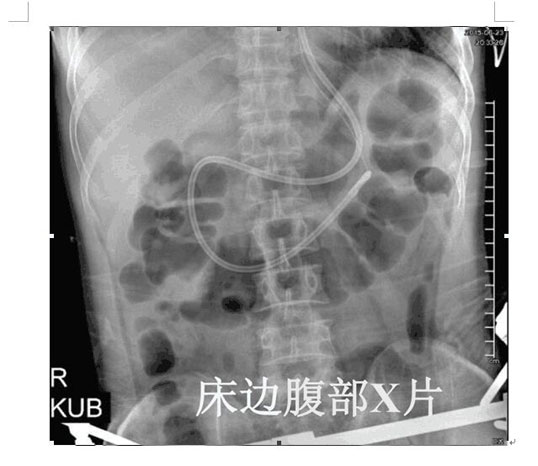

2017年4月22日,ICU成功開展了第一例床旁盲插經(jīng)鼻空腸管置入術并獲得成功。截止目前已為三位患者完成該術,均為一次性盲插置管成功,臨床反映良好。此項技術的成功應用,填補了我院在該護理技術領域的一項空白,標志著ICU的護理技術水平邁上了一個新的臺階。

以往選擇在X線下或者使用胃鏡協(xié)助置入鼻空腸管,患者痛苦大且受輻射影響。而床旁徒手盲插經(jīng)鼻空腸管植入術是臨床護士在不依賴于其他輔助設備的情況下,通過一定的置管技巧,將管道插至十二指腸或空腸。此法省時、費用低、操作方便、損傷小,尤其對胃蠕動功能差的患者,不易引起食物反流、誤吸。鼻空腸管不僅可以從管內(nèi)注入營養(yǎng)液,而且還可以進行胃腸減壓,值得臨床推廣。